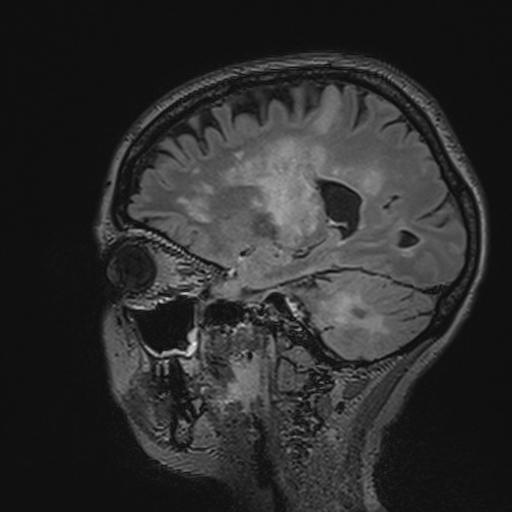

Researchers from the University of Zurich and the University Hospital Zurich reveal possible new treatment methods for a rare, usually fatal brain disease. Thanks to their discovery that specific antibodies play a key role in combating the viral infection, a vaccine against the disease "progressive multifocal leukoencephalopathy" could now be developed.

Humans carry a multitude of viruses and bacteria in their gut, on their skin and in other organs. Often, these are involved in important bodily functions. Under certain conditions, however, some can also cause diseases. The JC virus, a member of the polyoma tumor virus family, is a prime example. This pathogen was first isolated from the brain of a patient who was suffering from a rare brain disease known as progressive multifocal leukoencephalopathy (PML). The virus, which more than 60 percent of the global population are infected with, normally resides in the kidneys and certain other organs. JC virus can trigger the PML infection in the brain, which, in most cases, is fatal.

In multiple sclerosis (MS) patients, for instance, the treatment with a particular antibody, TysabriTM, prevents immune cells from reaching the brain - but at the same time, also inhibits the brain's immunosurveillance. If JC viruses enter the brain during the treatment, they go undetected, which can cause PML, the most significant side effect of the highly effective TysabriTM. Over 560 MS patients worldwide have already developed the PML brain infection. Over 20 percent of them died from the disease as there is no effective treatment to date. Only if the immune system function is completely restored can the JC virus be removed from the brain.